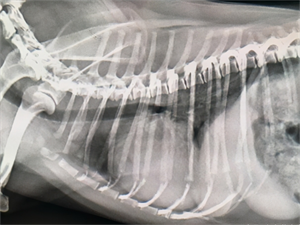

如果你发现自己家的狗狗有心脏病的症状或者害怕狗狗患有心脏病,可以带狗狗去做心脏部位的检查,一般医院的确诊方法包括临床问诊和仪器检查两种。

心脏类疾病的检查项目:

做心脏B超是必不可少的,平均来看,给宠物做黑白B超一次的价格在50-100元;

做彩超的价格一次在100-200元,而如果是做心脏方面的彩超检查,费用大约会在200元及以上;